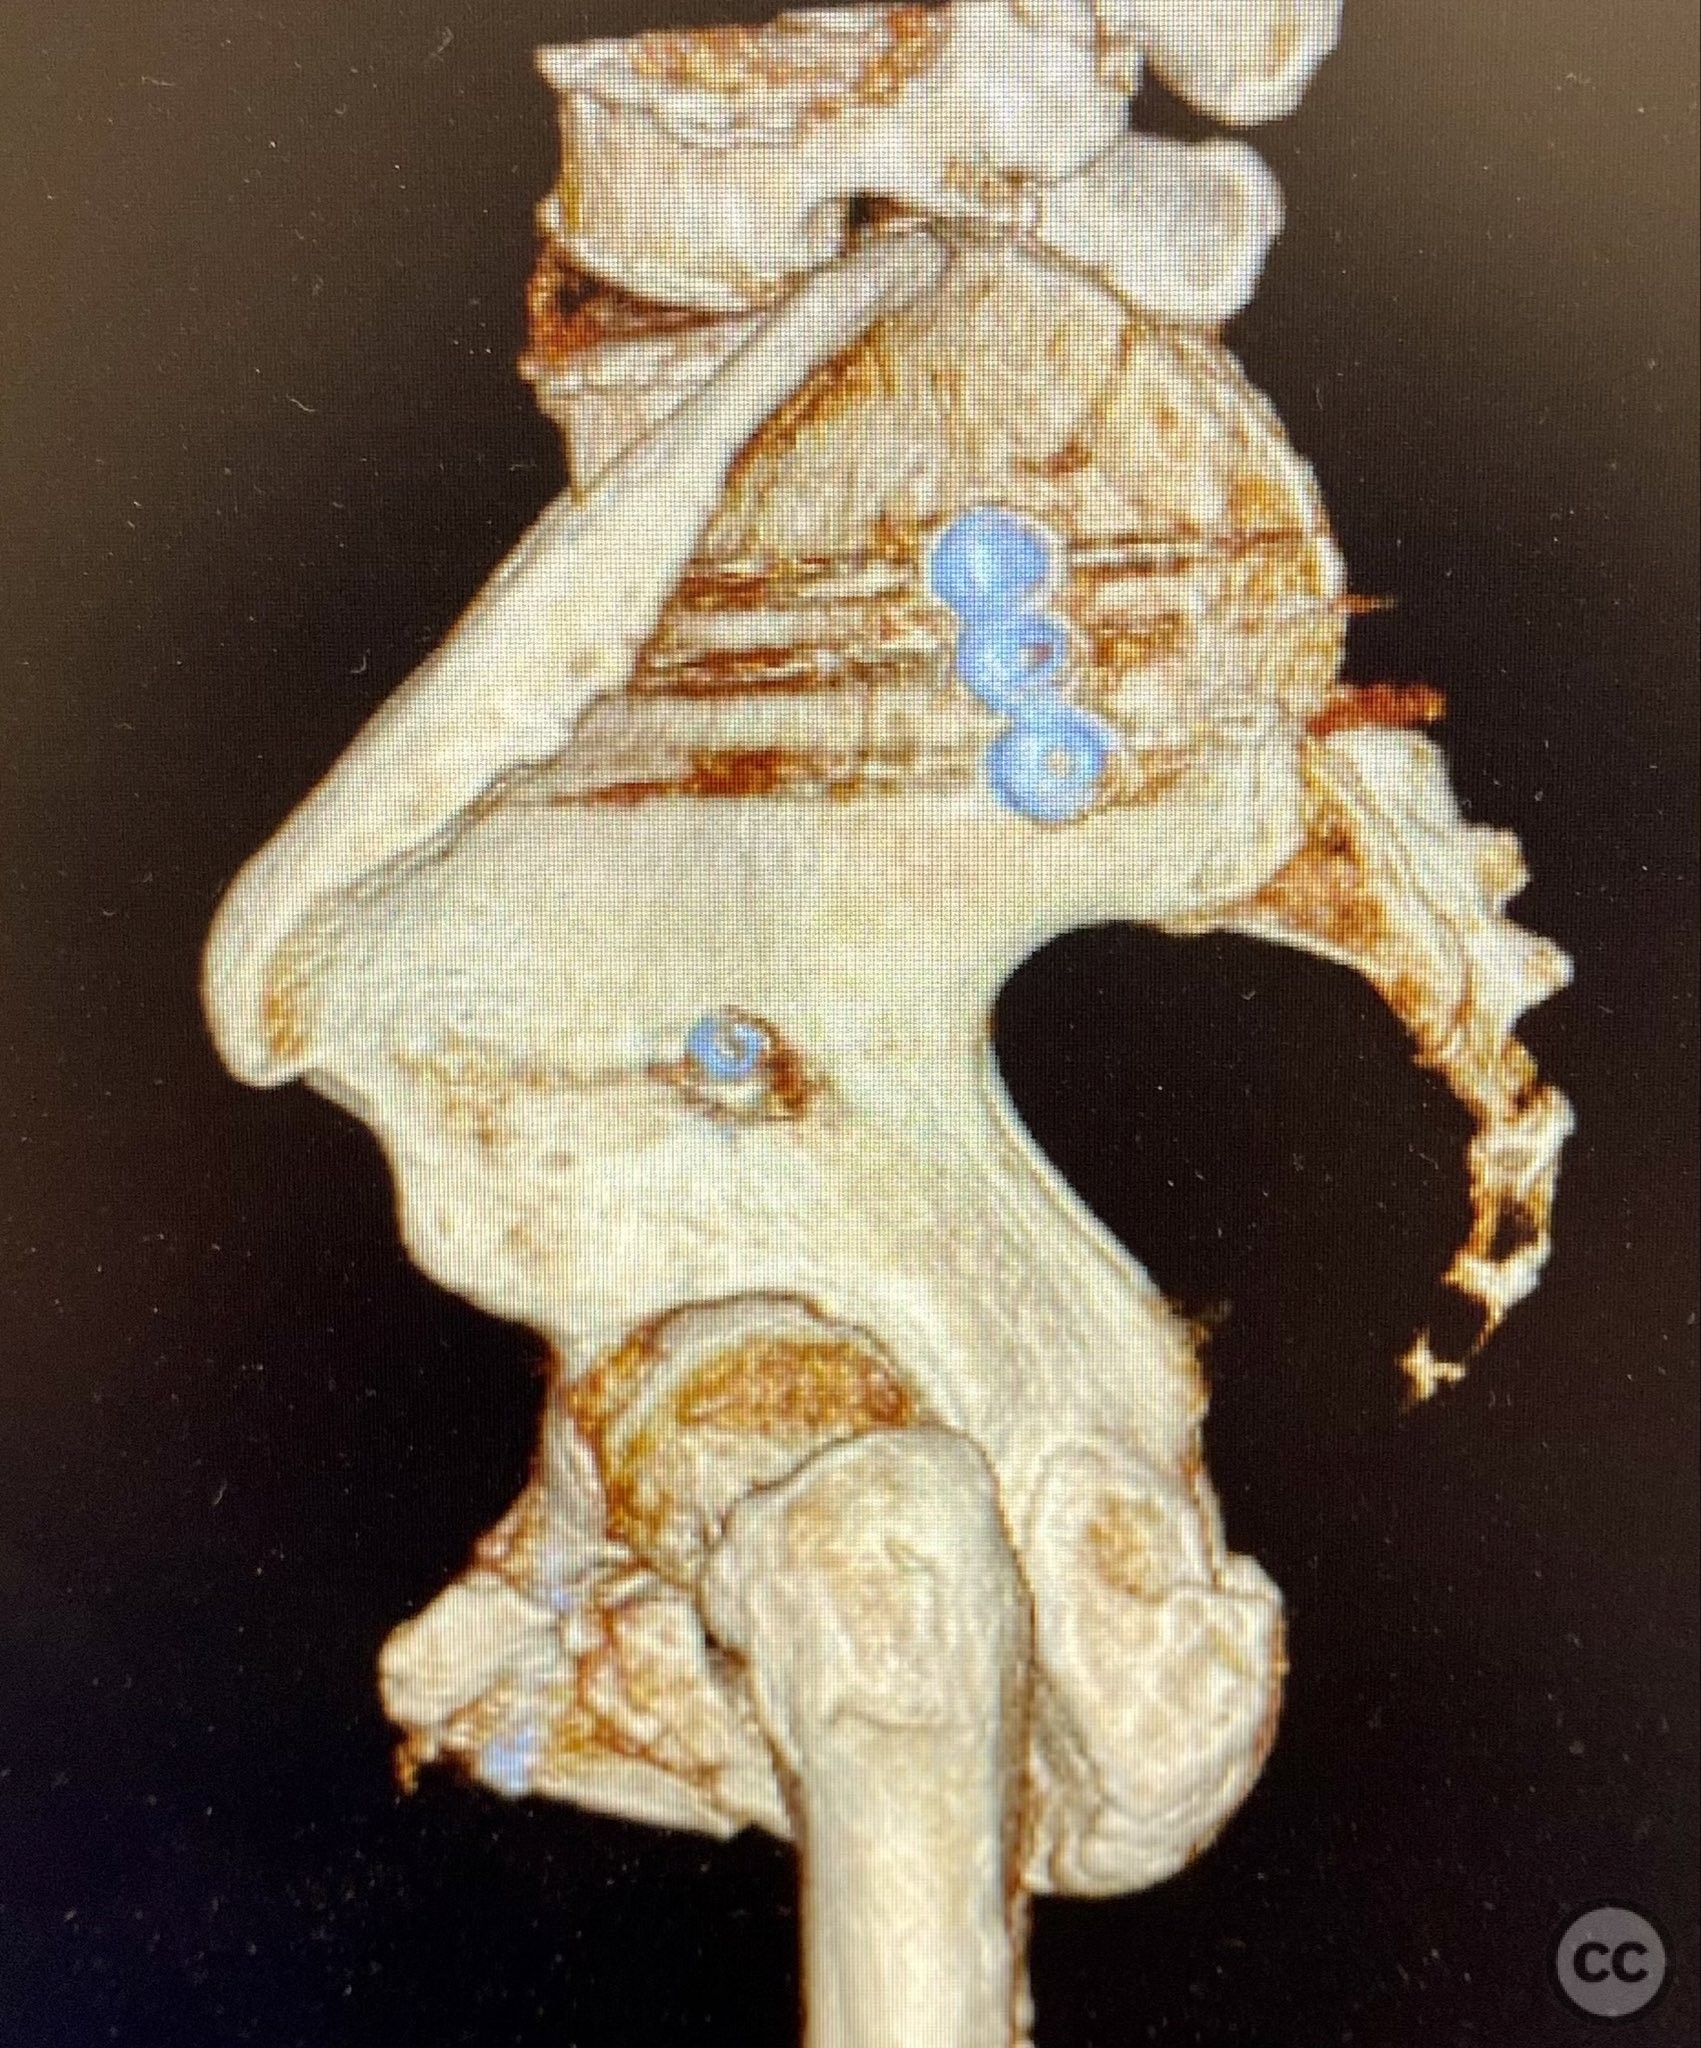

Clinical and radiological findings:  A 74-year-old female presented following a fall from standing height, unable to mobilize due to severe pelvic pain (9/10). Examination under anesthesia with fluoroscopic assessment (AP and inlet views) demonstrated instability and displacement of the pelvic ring with minimal manual compression at the iliac crests. Imaging revealed left-sided posterior iliac/sacral and pubic ramus fractures consistent with an AO/OTA 61-B2 (lateral compression type) pelvic ring injury. No neurovascular deficits were noted.

Planning remarks:  The preoperative plan involved closed reduction of the pelvic ring under fluoroscopic guidance, followed by percutaneous screw fixation of the left posterior iliac/sacral region and the ipsilateral pubic ramus. Detailed preoperative CT imaging was used to plan safe osseous corridors for screw placement, correlating with intraoperative fluoroscopic landmarks.

Anatomical surgical approach:  Percutaneous technique was employed. Small stab incisions were made over the lateral aspect of the pelvis. Under continuous fluoroscopic guidance, guidewires were advanced through the ilium into the sacrum (iliosacral region) and through the superior pubic ramus. Cannulated screws were then inserted over the guidewires, ensuring extra-articular and intraosseous positioning within the safe bone corridors as determined by preoperative CT analysis.

Orthopaedic implants used:   Cannulated iliosacral screw, cannulated pubic ramus screw